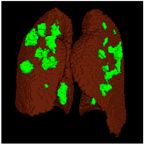

- By using a 3D segmentation architecture on a CT-scan, in addition to being able to help the COVID-19 disease diagnosis process, the 3D output generated from the model can help medical personnel determine the severity of the disease, such as mild, moderate, or severe, through a 3D infection projection that can be easily seen from the output model that generates a file in 3D shape.

Based on the results of the evaluation metrics for each architecture in Table 5, surprisingly, 3D UNet is better than the other six methods. Compared with the 3D VGGUNet architecture with transfer learning, which achieved the second best result on average, 3D UNet improved by 0.37%, 0.23%, 0.03%, and 0,19% in IoU score, Dice score, accuracy, and F1-score, respectively. Although 3D UNet has the best evaluation of metrics compared to other architectures, 3D UNet has the longest maximum learning iteration process of 1663, in contrast to other architectures, which are modifications of 3D UNet, and which have an average maximum learning iteration of 278. Of the seven models that have been tried, 3D DenseUNet obtained first place as the architecture with the fastest learning time, ±4459 s and ±6539 s without transfer learning and using transfer learning, respectively. The 3D UNet architecture stays in the second last position with a learning process time of ±17,217 s, and for the position of the architecture that has the longest training process, it is the 3D VGGUNet, with transfer learning reaching ±23,200 s. The comparison of loss training and testing on the 3D UNet learning process for the lung segmentation is shown in Figure 4. Furthermore, in Table 6, the comparison of ground truth and the prediction results of the 3D UNet model in 2D (slice) and 3D projections for this binary-class segmentation case can be seen.

Table 6.

Comparison between ground truth and prediction results of lung segmentation with 3D UNet architecture.

Table 8.

Comparison between ground truth and prediction results of lung and infection segmentation with 3D UNet architecture.